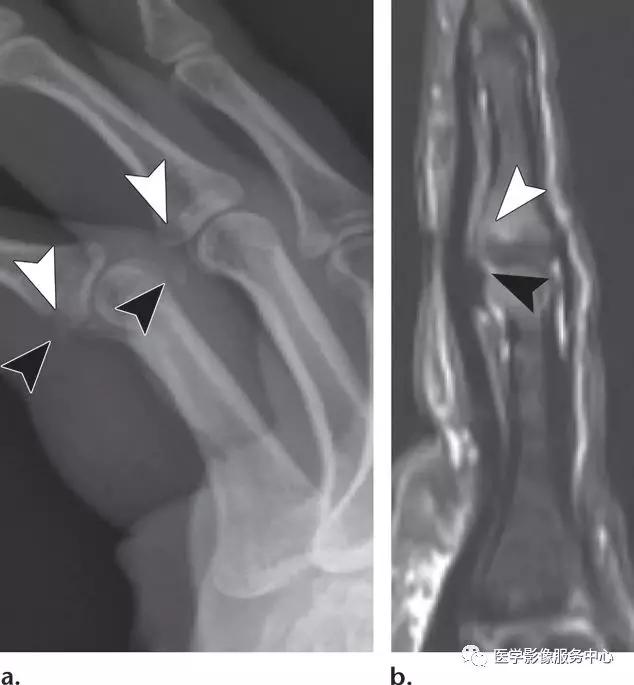

桡侧副韧带撕脱损伤:

(左)撕脱骨片略示移位(白色箭头),累及桡侧副韧带在第一近端指骨桡侧基底部的连接处。(右)桡侧副韧带从其指骨连接处的部分层厚撕裂(白色箭头),不伴有撕脱骨折。注意尺侧副韧带损伤也存在(白色长箭头)